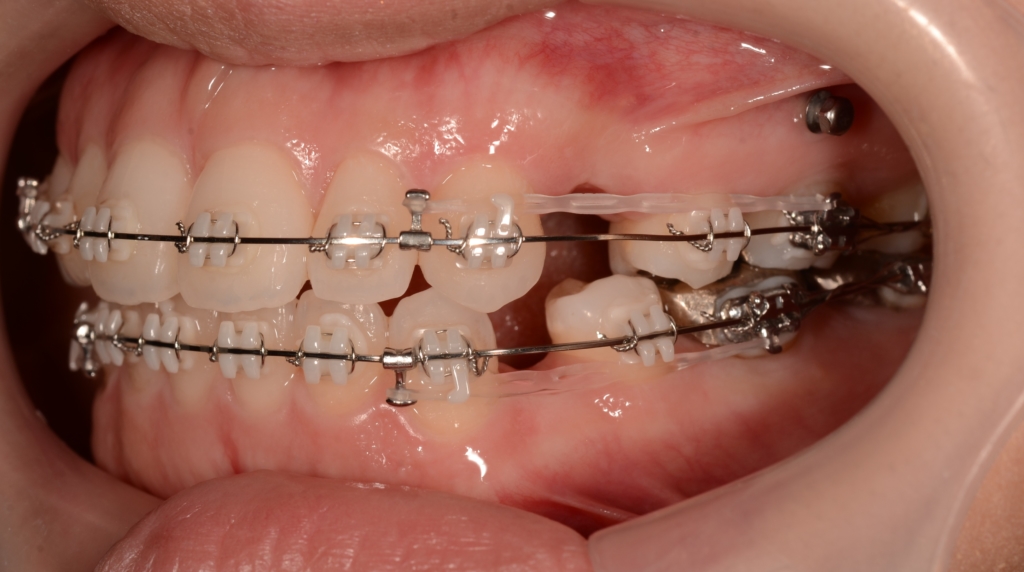

マルチブラケットシステム(スタンダードtype)で矯正を開始。

上の歯列がきれいに並んで、アンカースクリューを植立する目途がついたので、上顎の口蓋正中部、臼歯部と前歯部の頬側辺りにアンカースクリューを植立しました。(計6本)

ただ、せっかくアンカースクリューを植立したので、臼歯部の圧下だけでも行い、下顎の反時計回りの回転によるオトガイ部の前方移動(→ Eラインを引くうえで有利になる)と、前歯部の開口傾向の改善だけは図ることにしました。 この作戦だと時間を短縮できます。

奥歯の圧下による下顎の反時計回りの回転を狙っています

前歯部の噛み合わせに目途が付いた時点で、下の歯にも装置を付けて、合わせて治療を進めます。

噛み合わせがしっかりしたところで、上下とも第一小臼歯を抜歯して前歯を後方へ最大限に引っ込めて行きます。